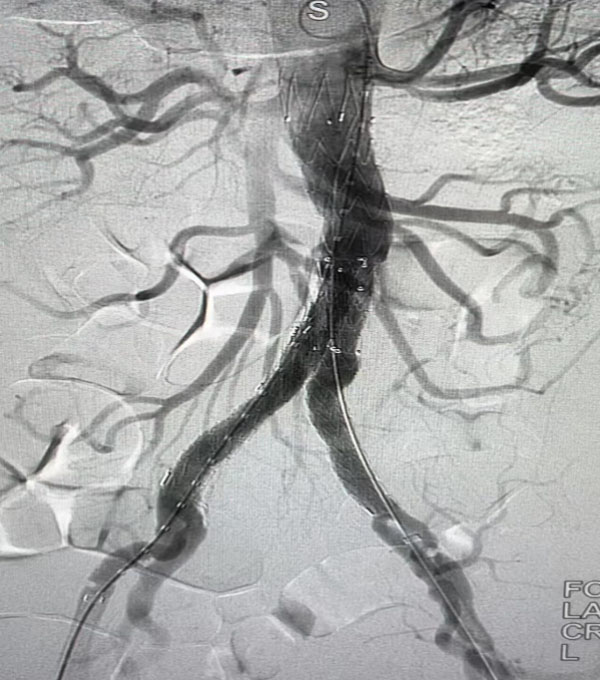

同期,另一台“升主动脉置换+全主动脉弓置换+胸主动脉覆膜支架腔内隔绝术”正在开展,该病例为一名A型主动脉夹层患者。在主动脉弓及分支成功游离且心脏停跳后,心外科负责人赵永波“转场”为患者完成了血管置换,心脏复跳成功,止血彻底。随后,谈凌凌主治医师、侯五辉主治医师为患者进行胸主动脉腔内修复。下午2点左右,两台手术成功结束。通过现场视频直播,在手术同时,手术人员与大会现场的专家们就影像评估、手术策略、手术器械的选择及操作技巧等多个环节进行了互动讨论,学术气氛热烈,大会主席及与会代表给予我院高度评价。紧接着,手术团队又为一名79岁腹主动脉瘤患者进行了腹主动脉腔内修复手术,效果良好,同样受到与会专家的好评。

腹主动脉腔内隔绝